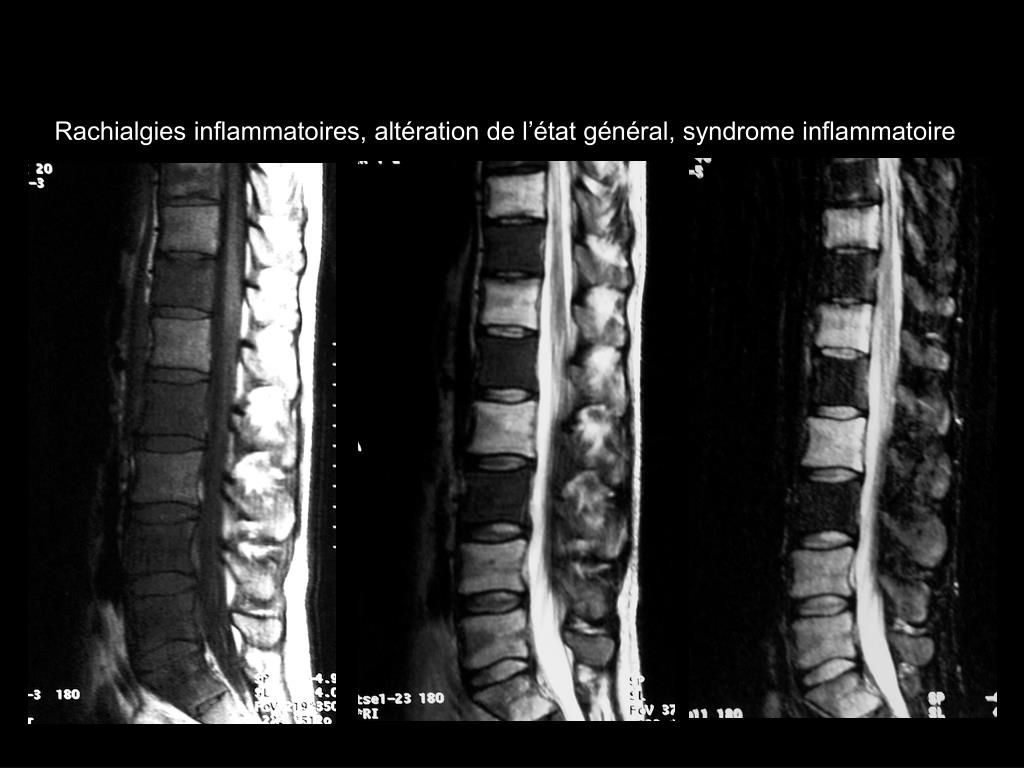

17. Rachialgies inflammatoires, altération de l’état général, syndrome inflammatoire

18. Rachialgies inflammatoires, altération de l’état général, syndrome inflammatoire

19. Spondylites dans le cadre d’une maladie de Crohn!